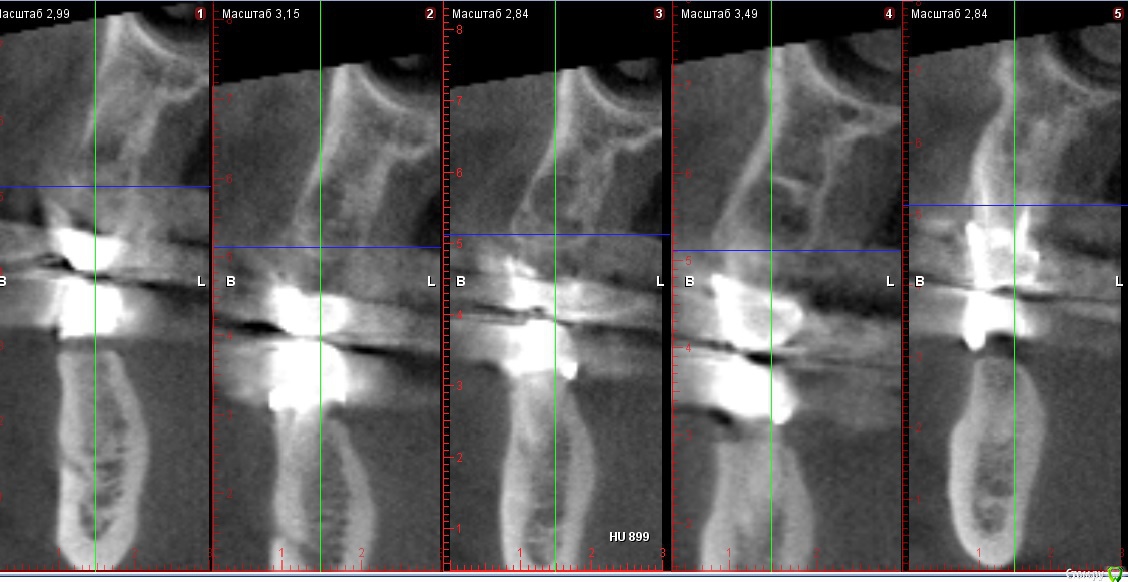

Мк стоят около 10 лет,в области 23 средней 1/3 определяется свищ,отделяемого нет,небольшое западение альвеолярного отростка с рубцовыми изменениями слизистой в области 24 ,перкуссия 23,25 безболезненна,болезненность в области переходной складки и небной поверхности на уровне апекса 23

Со слов пациента периодически возникающий отек,тянущие боли

Около недели назад был похожий случай: пациент мост 1.6-1.4. В промежутке неясного генеза убыль кости по снимку. Делаем КТ - очаг просветления в области отсутсвующего зуба, по снимку  вроде кость 4 типа. Объясняю пациенту, что будем ставить имплантат, раскроемся и увидим что там. День Х, после отслоения в области удаленного зуба 1.5 грануляционная ткань! 30 минут кюретажа всех этих спаек и получена практически первоначальная лунка удаленного зуба 1.5. Закинул кость и вкрутил имплантат. Ушил, а на момент когда пациент вышел из кресла - сказал, что сало прям легче. мол было даже желание вам доктор помочь все это из лунки убрать))) 2 недели все гуд - ничего не беспокоит. Так вот к чему так много букав: скорее всего удалили зуб и не сделали кюретаж, там грануляционная ткань которая дает всю эту картину. Побольше бы срезов с КТ. И сделайте сагитальные срезы. Если полость из неоткуда то режьте и смотрите.